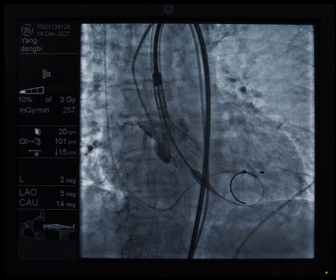

造影观察瓣膜形态

术后造影及超声探查未见瓣周漏,跨瓣压差术前47mmHg,术后几乎无压差,术中及术后未出现相关并发症,手术圆满完成。

经过何泉主任医师团队一个小时的通力协作,手术顺利完成,患者血流动力学即刻改善,无并发症的发生,极大提升了患者的生活质量。